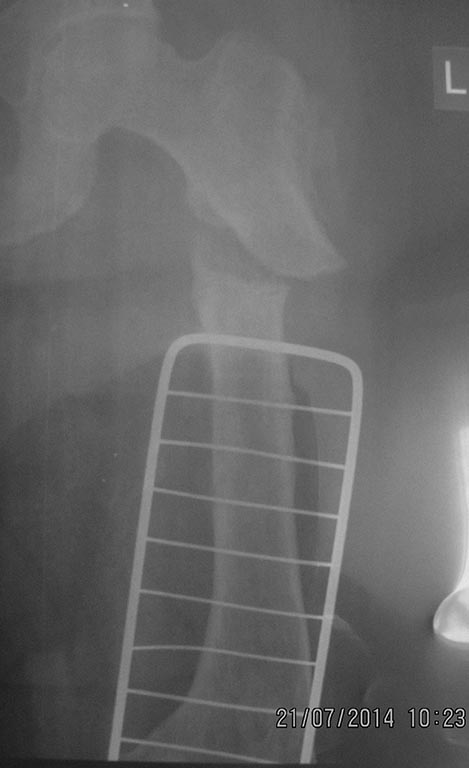

[Ortho] перелом бедра с исходной деформацией

Имя     : IMG_2891.jpg

Тип     : image/jpeg

Размер  : 44480 байтов

Url     : http://weborto.net:8080/pipermail/ortho/attachments/20140721/a09be377/attachment-0008.jpg